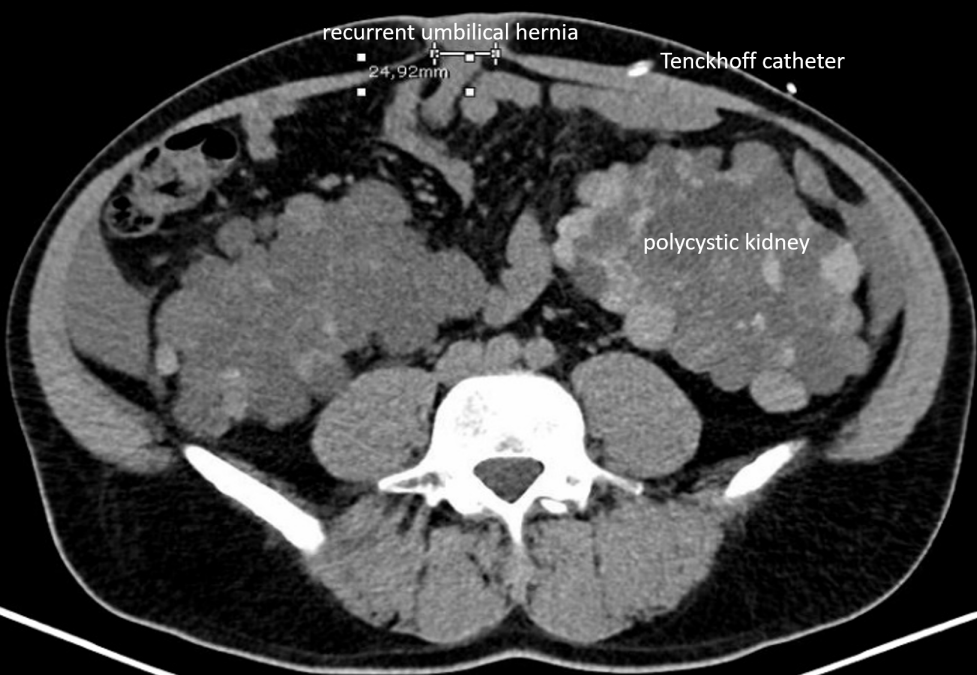

We report a case of a robotically assisted enhanced-view totally extraperitoneal hernia repair (eTEP) of a recurrent umbilical hernia, performed on a 43-year-old male patient with polycystic renal disease and PD. The patient presented with a 2.5 x 2 cm recurrent umbilical hernia, associated with a 3.5 cm diastasis recti and an additional epigastric hernia. The year before suture repair of aforementioned umbilical hernia was performed during the implantation of the Tenckhoff catheter. An additional suture repair of another epigastric hernia between both hernia localisations prior to implantation of the catheter was reported. The patient had a BMI of 31 and no further comorbidities other than epilepsy. Ultrasound examinations showed that the catheter was implanted close to the umbilicus while passing the retrorectal space more caudally (Figure 1 [Fig. 1], Figure 2 [Fig. 2]). Hence we concluded that a retrorectal mesh placement with an overlap of at least 5 cm should be possible.

Figure 1: CT scan preoperative